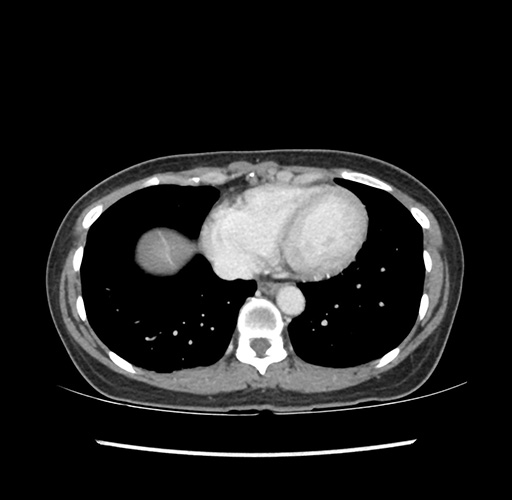

Imaging Analysis

Look through the patient's CT scan to identify any areas of concern for the necessary procedure.

Based on your CT findings, which issue(s) would give reason for "planned slowing down moment(s)" in this case?

Considering a standard left lateral sectionectomy procedure, what step(s) of the operation would you do differently in this case ?